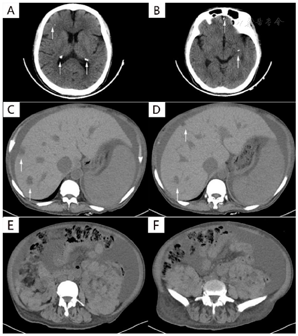

完善头部平扫CT提示双侧脑实质及侧脑室管膜下多发结节状钙化灶(图2 A、B),MRI提示双侧脑实质及脑室室管膜下多处异常信号灶。胸腹盆平扫CT提示心影明显增大,心包积液;腹盆腔大量积液;肝脏多发低密度影,门脉增宽,脾脏增大(图2C-D);双肾正常结构消失,密度混杂(图2E、F),结合患者当地医院腹部增强CT,患者肝脏、肾脏考虑为多发平滑肌血管脂肪瘤。患者血常规提示全血细胞减少;心电图示不完全性右束支传导阻滞;超声心动图发现三尖瓣四叶瓣畸形、三尖瓣瓣环扩张、三尖瓣重度关闭不全,因患者无法耐受未能进一步完善心肌灌注延迟成像动态MRI;为明确全血细胞减少的原因,完善骨髓穿刺,骨髓涂片提示红系中、晚幼红细胞比例增高,可见大红细胞。胃镜检查未见食管、胃底静脉曲张。基因检测明确TSC2基因变异。患者育有3女,其中1女具有类似的面部血管纤维瘤、足趾纤维瘤和癫痫症状。